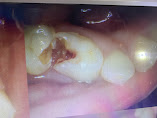

२) Enamel Caries: यो चरणमा अम्लले पारेको प्वाल दाँतको बाहिरी पत्र अथवा Enamel मा सिमित रहन्छ ।

३) Dentinal Caries: यो चरणमा अम्लले पारेको प्वाल दाँतको भित्री पत्र अथवा Dentin सम्म फैलिसकेको हुन्छ । Dentin, Enamel भन्दा नरम हुने भएकोले यो भागबाट किराले खाने प्रकृया चाडो फैलिन्छ ।

४) Pulpitis: यो चरणमा दाँत किराले खाने प्रकृया दाँतको नशा अथवा Pulp सम्म फैलिसकेको हुन्छ । यो चरणमा दाँतको दुखाई सुरुभइसकेको हुन्छ ।